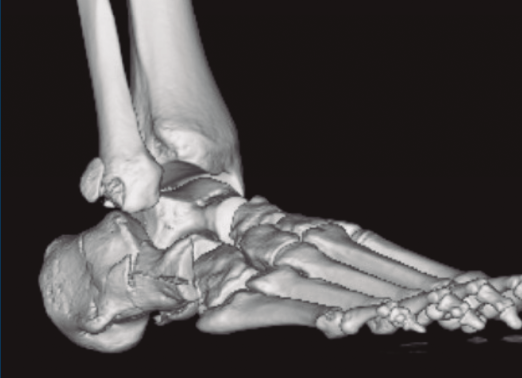

Figura 1. Luxación del astrágalo en mortaja tibioperonea, fractura maléolo peroneo y espacio subperoneo ocupado por calcáneo.

Se trata de un varón de 19 años que ingresa en reanimación tras precipitarse desde una altura de aproximadamente 10 metros. El paciente presenta una fractura estallido de L3 con afectación del canal medular junto con una fractura del vértice inferior de L4, así como una fractura luxación de calcáneo, asociada a una fractura del maléolo peroneo y del maléolo tibial posterior (Figuras 1 a 6) diagnosticadas mediante TC total body (por eso no se dispone de radiografías simples al momento del ingreso). Como podemos comprobar, se trata de una fractura de doble trazo de tipo hundimiento/depresión de la carilla articular (Figuras 5 y 6).

Figura 4. Luxación fragmento posterolateral.